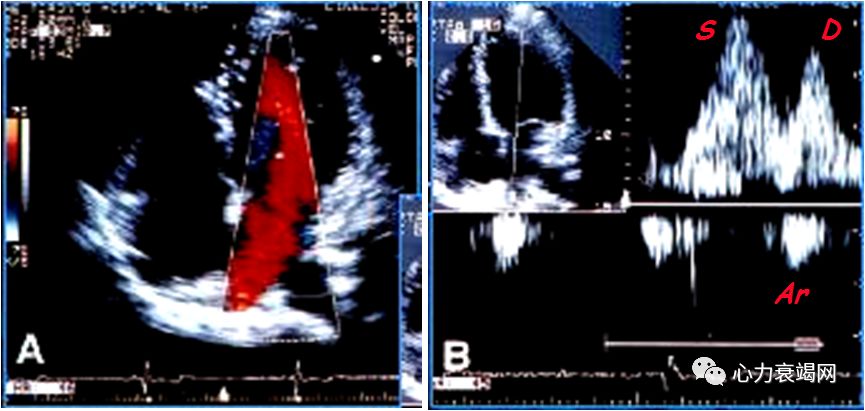

检测前提:窦性心律,连接ECG获得清晰肺静脉血流频谱

检测指标:S/D比值,PV频谱Ar时间

取心尖四腔切面,启动CDFI并调整M型取样线通过二尖瓣口至心尖使之与舒张期充盈血流平行,然后启动M型成像,在窦性心律者显示两个与E和A相关彩色血流,测量舒张早期充盈血流出现彩色混叠颜色变化前缘向心尖方向延伸4cm处的斜率。

E / Vp>1.5 时 LA 压力增高。

AMI 后E / Vp<1.5者的预后明显好于E/ Vp≥1.5者。

有报道E/ Vp预测AMI 后发生心衰及死亡的价值优于EF。